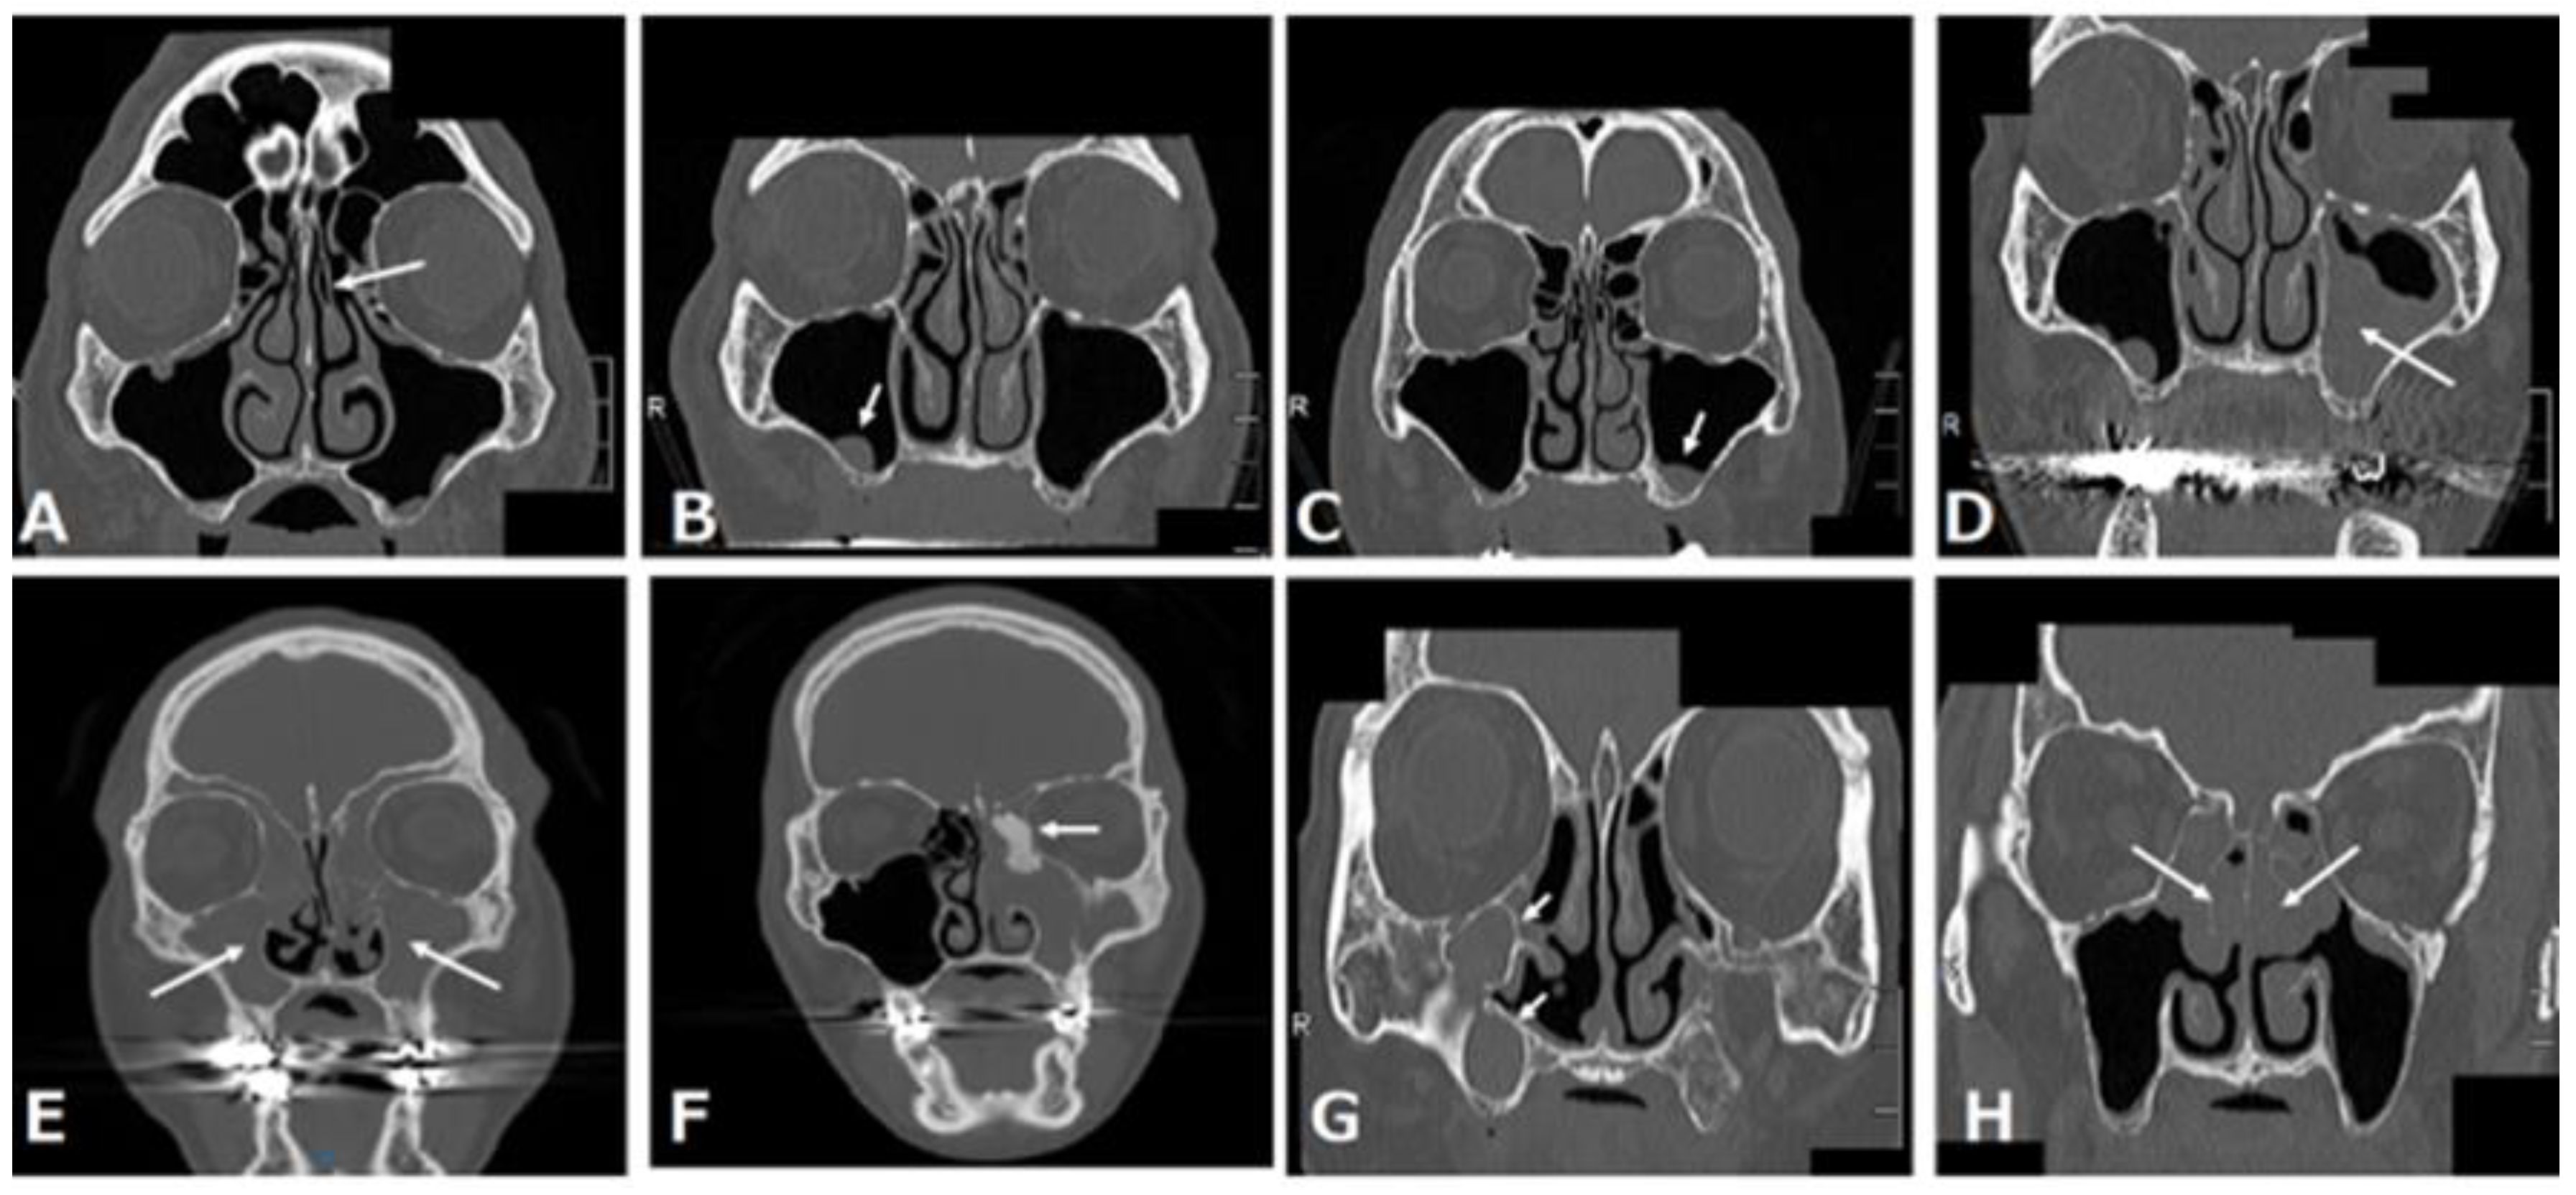

3.1. Retention Cyst or Solitary Polyp

3.2. Mucosal Thickening in the Maxillary Sinus

3.3. Acute Rhinosinusitis

3.4. Chronic Rhinosinusitis

3.4.1. Neutrophilic Chronic Rhinosinusitis

3.4.2. Neutrophilic Chronic Rhinosinusitis with a Benign Tumor Such as Osteoma

3.4.3. Eosinophilic Chronic Rhinosinusitis (ECRS)

3.5. POMC